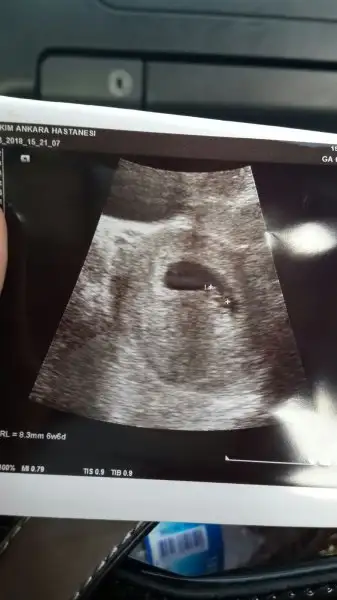

Karından muayeneMerhaba kızlar arkadaşım attı yorum yapar mısnız 6+5

KızMerhaba kızlar arkadaşım attı yorum yapar mısnız 6+5